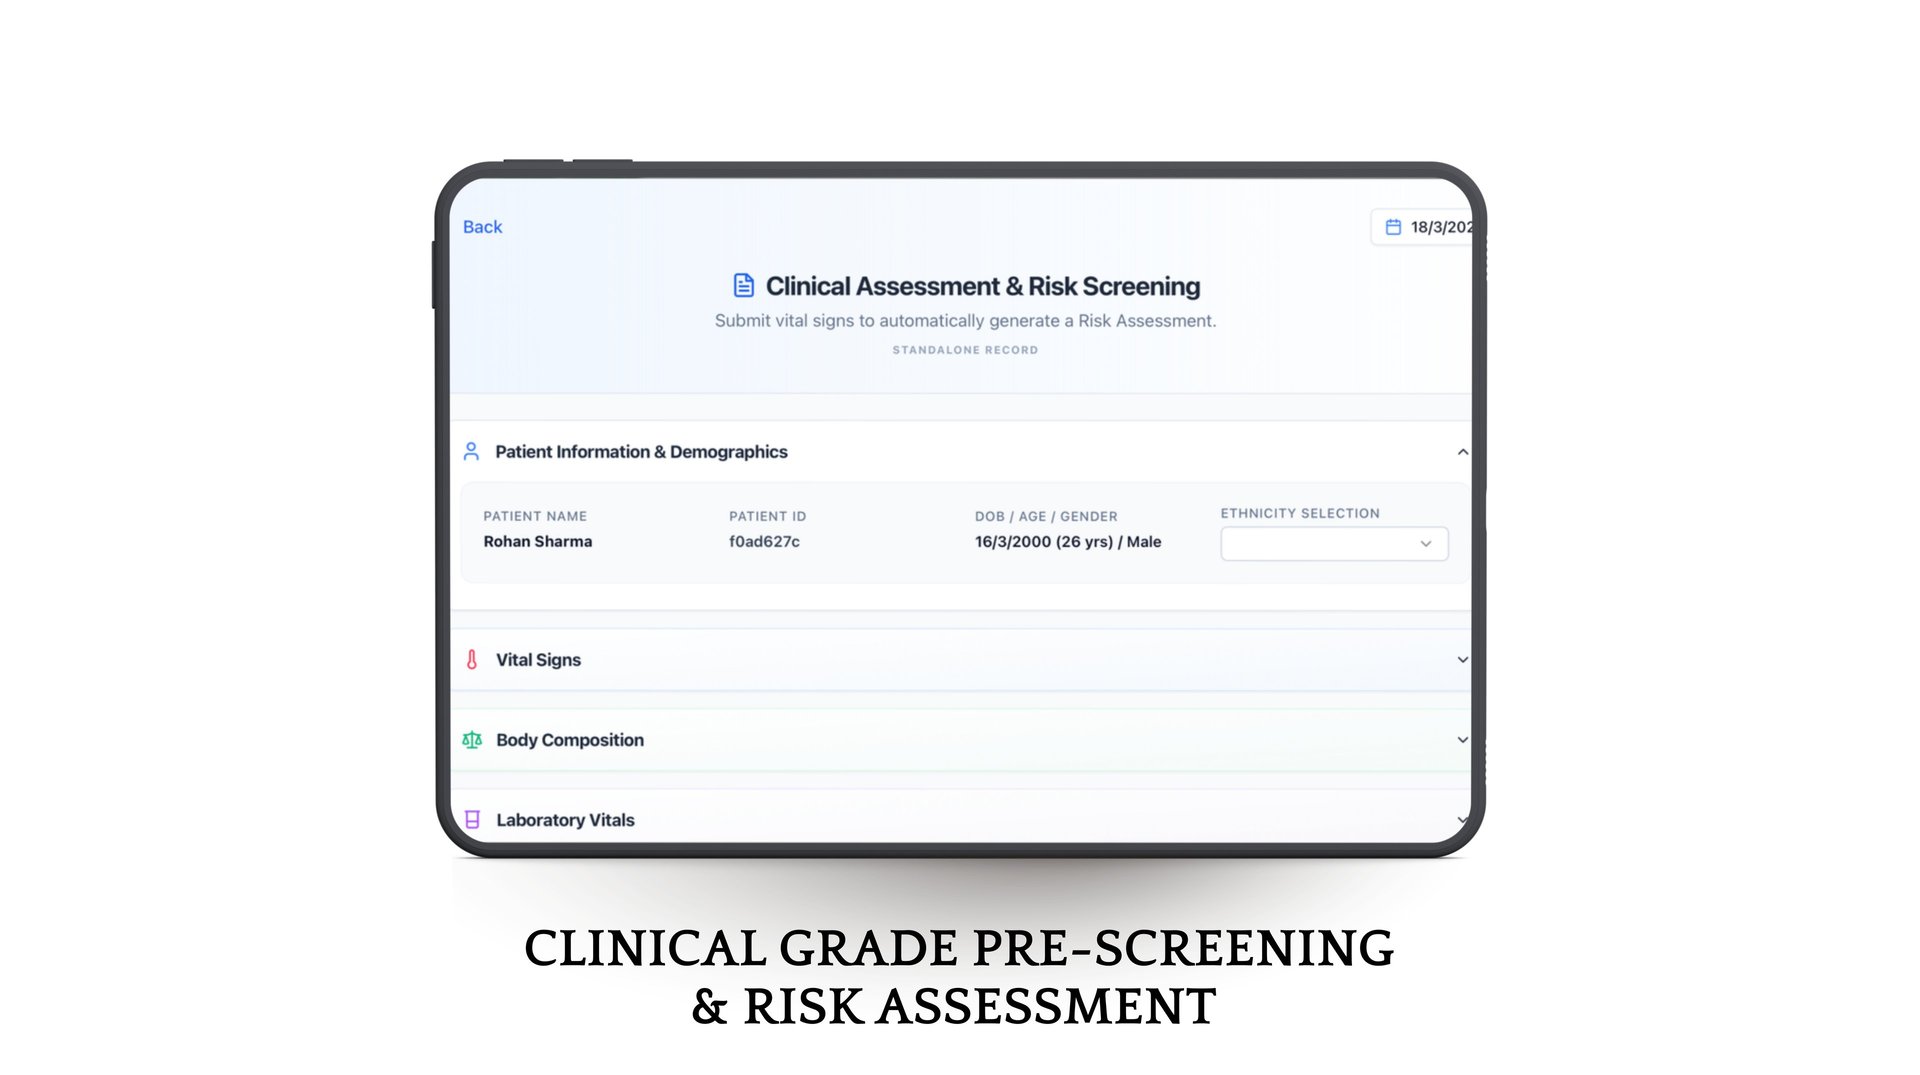

Phia.Care's Risk Assessment Models

Phia.Care's Risk Assessment Models use clinically recognized algorithms, including WHO-based risk evaluation frameworks, to analyze patient screening data and generate structured health risk insights.

By evaluating vitals, demographics, and other screening parameters, the system creates a standardized risk profile for each patient and assigns a confidence score based on data completeness. This helps clinicians quickly understand potential health risks and support early, informed medical decisions.